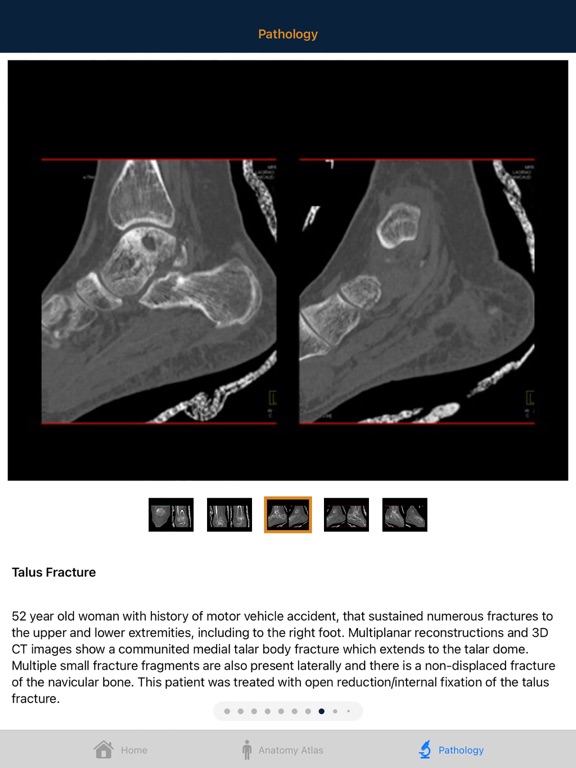

Understanding complex bony Anatomy and Pathology of the Foot and Ankle is essential to the interpretation of musculoskeletal CT. The anatomy of the ankle is complex and in the past CT evaluation of the ankle was often limited to axial slices and simple multiplanar reconstructions. However improvements in CT scanning technology now allow thin collimation and isotropic datasets. These advances along with easy to use 3D software have improved our ability to image the ankle with volume display. It is important for the radiologist to be familiar with the anatomy in all 3 dimensions. This atlas aims to educate the radiologist with respect to normal and pathological anatomy through case studies and artist rendered interactive 3D models and illustrations. Radiology professionals will have a better understanding of ankle and foot bony anatomy after using this atlas. We hope you enjoy it.